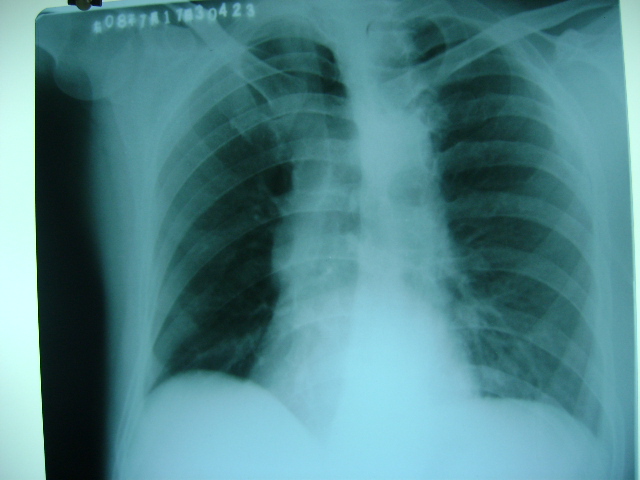

标题: X4564:右位心可能吗

m47y外伤发现

脊柱侧玩畸形,同事怀疑,本人不支持

看起不像哦,脊柱侧弯畸形重叠引起,主动脉弓影在左侧。

胸片类似斜位,心影右旋,应该可否定右位心吧。

轻度左前斜位造成的假象。

不可能为右位心,脊柱侧弯,胸廓畸形所致.

胸廓不对称,脊柱侧弯,导致心脏位置改变,请注意主动脉结,心尖位置,肯定不是右位心.